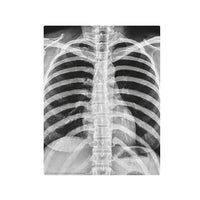

Build a full human skeleton set, complete as glow magnets. Learn how the skeleton supports our body. Includes “magic” x-ray films that let you “see through” the human body!